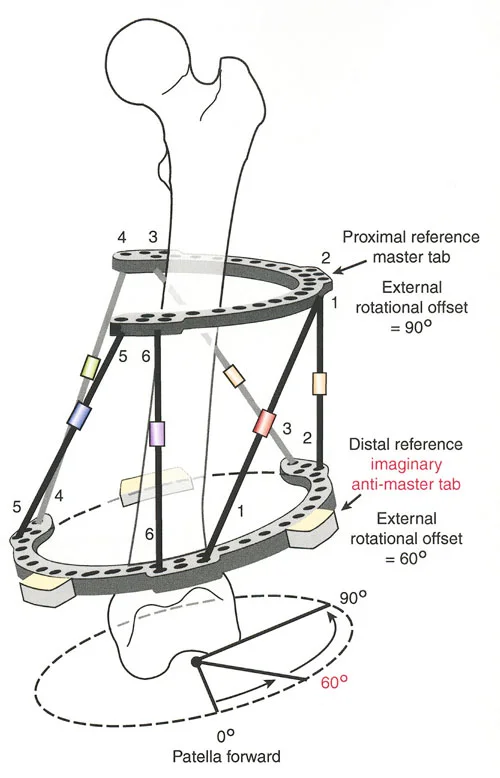

- مثبتات إليزاروف الدائرية الكلاسيكية: تتكون من حلقات معدنية متصلة بالعظم بأسلاك رفيعة، وتسمح بتصحيح متعدد المستويات.

- أنظمة الهيكسابود الحديثة (مثل جهاز تايلور الفراغي Taylor Spatial Frame): تستخدم ست دعامات متداخلة (struts) متصلة بحلقتين. يتم التحكم فيها بواسطة برنامج حاسوبي يقوم بحساب التعديلات اليومية بدقة فائقة لتصحيح التشوه في ستة اتجاهات.

إتقان معدلات الشد: قاعدة المثلثات المتشابهة

القاعدة الذهبية البيولوجية لتوليد العظم بالشد، التي وضعها إليزاروف بعد عقود من التجارب على الحيوانات والبشر، هي معدل شد يبلغ 1 ملم يوميًا. يتم تقسيم هذا عادة إلى زيادات قدرها 0.25 ملم كل 6 ساعات لمحاكاة النمو المستمر للوحة النمو.

ومع ذلك، فإن الخطأ الشائع، الذي قد يكون كارثيًا أحيانًا للجراحين المبتدئين، هو سوء فهم أين يجب أن يحدث هذا الـ 1 ملم يوميًا.

معدل 1 ملم/يوم ينطبق بشكل صارم على القشرة المقعرة للعظم في موقع قطع العظم (الحافة الأمامية للإسفين المفتوح). نظرًا لأن الجهاز (قضيب الشد أو دعامة TSF) يقع على مسافة من العظم، خارج غلاف الأنسجة الرخوة، فإنه يتحرك على طول قوس أكبر بكثير. إذا وجهت المريض لشد القضيب بمعدل 1 ملم يوميًا، فإن العظم الفعلي سيُشد بجزء ضئيل من هذا المعدل، مما يؤدي إلى التصلب المبكر لموقع قطع العظم.

حساب معدل الشد الحقيقي

لحساب المعدل الصحيح للشد عند المفصلة، نستخدم قاعدة المثلثات المتشابهة، والتي تعتمد أساسًا على القاعدة الهندسية للدوائر متحدة